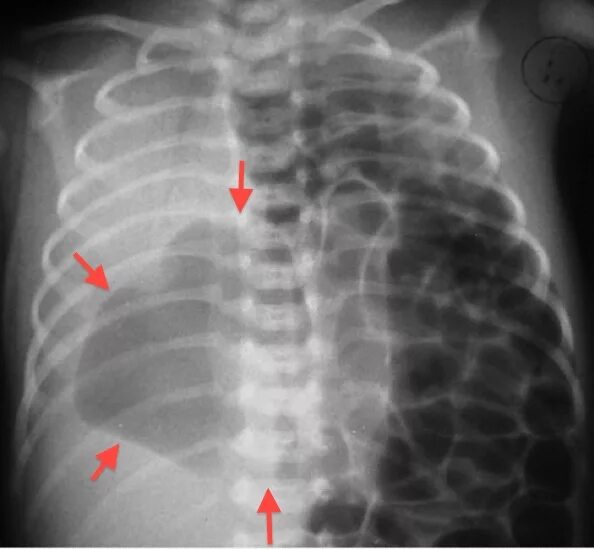

Гипоплазия 12 пары ребер